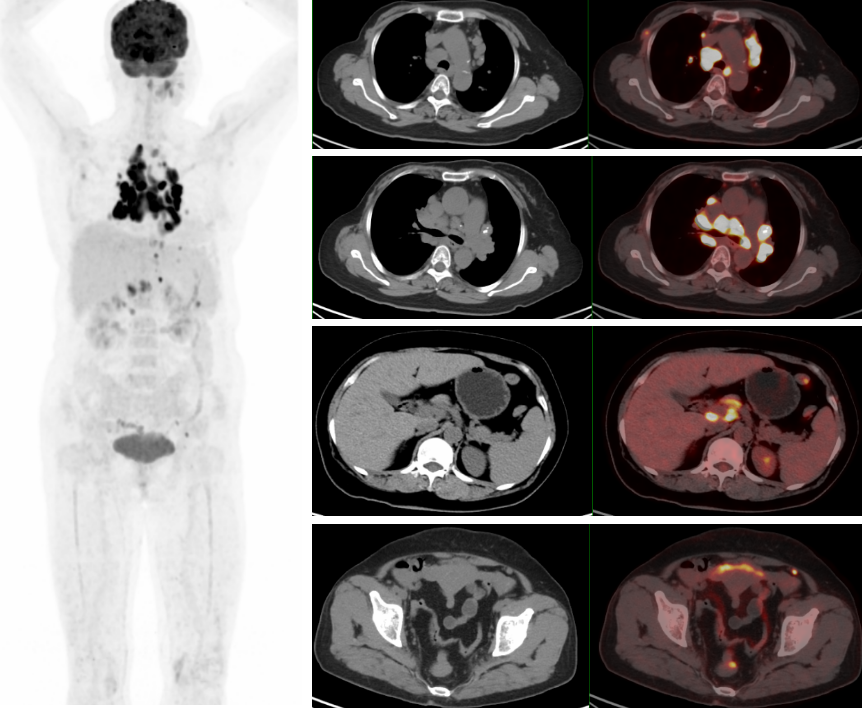

PET/CT示:雙側(cè)鎖骨上、縱隔、胸骨后、雙肺門、雙側(cè)肋骨旁、腹腔、腹膜后、盆腔及左側(cè)腹股溝見多枚代謝異常增高淋巴結(jié),較大者約3.4×2.1cm,SUVmax約20.7。

PET/CT診斷:考慮結(jié)節(jié)病,建議病理檢查。

此例患者由于乳腺癌的病史,臨床初步懷疑轉(zhuǎn)移。PET/CT顯示縱隔、肺門淋巴結(jié)腫大,且呈對稱性分布,密度均勻,邊界清晰,無明顯融合,F(xiàn)DG高攝?。淮送饪梢姸喟l(fā)腹盆部,頸部淋巴結(jié)次之,分布較散,體積及FDG攝取小于縱隔和肺門淋巴結(jié),也不是乳腺癌術(shù)后易轉(zhuǎn)移的部位。綜上考慮符合結(jié)節(jié)病表現(xiàn),最終得到病理證實,患者因此避免了不必要的抗腫瘤治療。